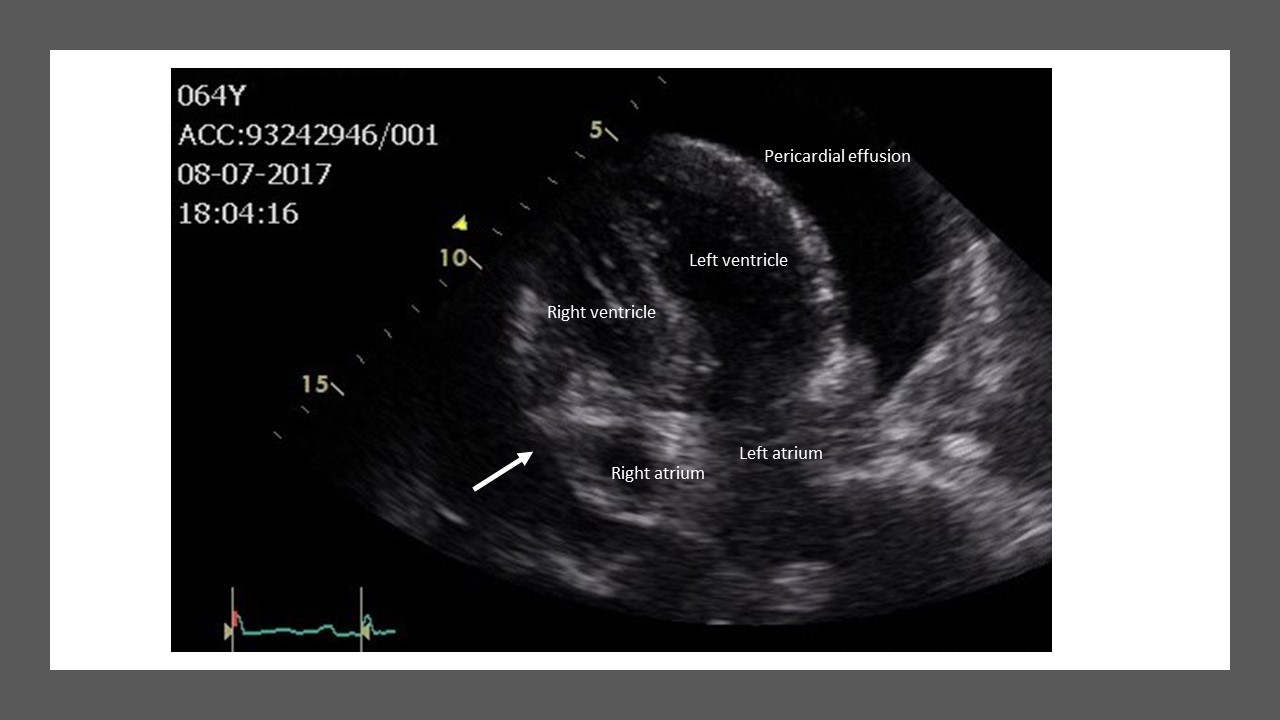

Prompt diagnosis is the key to reducing the mortality risk for patients with cardiac tamponade. Although cardiac tamponade is a clinical diagnosis, echocardiography (Figure 2) provides useful information and is the cornerstone during evaluation (availability, bedside, and treatment). However, cardiac tamponade is associated with a variety of abnormalities that lead to changes on the electrocardiogram (ECG), chest X-ray, and on echocardiography. Abnormalities of tamponade on the ECG are typically low voltage and electrical alternans. However, reduced voltage can also be seen among other conditions such as infiltrative myocardial disease and emphysema, whereas electrical alternans characterised by beat to beat alterations in the QRS complex caused by swinging of the heart is specific, but not sensitive for tamponade. The chest X-ray reveals a normal cardiac silhouette until the effusions are at least moderate in size (~200 mL). In general, an enlarged cardiac silhouette is neither sensitive nor specific for the diagnosis of cardiac tamponade.

Echocardiographic techniques remain the standard non-invasive method to establish the diagnosis and can be used to visualise ventricular and atrial compression abnormalities as blood cycles through the heart [14]. An effusion appears as a transparent separation between the parietal and visceral pericardium during the cardiac cycle. Physiologic pericardial fluid may only be visible during ventricular systole, whereas effusions exceeding 75-100 mL are visualised throughout the cardiac cycle.

Figure 2.Two-dimensional echocardiogram illustrating cardiac tamponade with right atrium collapse or indentation (arrow).

The following may be observed with two-dimensional echocardiography:-

1) Early diastolic collapse of the right ventricular free wall

2) Late diastolic compression/collapse of the right atrium

3) Swinging of the heart in the pericardial sac

4) Dilated inferior vena cava with minimal or no collapse with inspiration

5) A greater than 40% relative inspiratory augmentation of blood flow across the tricuspid valve

6) A greater than 25% relative decrease in inspiratory flow across the mitral valve

7) Septal bounce into the left ventricle during inspiration